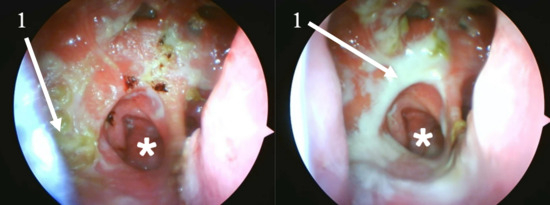

Background and Clinical Significance: Atrophic rhinitis (AR) is a rare, chronic inflammatory condition characterized by progressive atrophy of the nasal mucosa and underlying bone. The present report describes a case of severe secondary AR as a sequela of COVID-19-associated necrotizing rhinitis, highlighting the diagnostic and management challenges posed by multi-drug resistant pathogens and extensive anatomical destruction. Case Presentation: A 75-year-old female developed progressive necrotizing rhinosinusitis with osteomyelitis following a COVID-19 infection. Computed tomography (CT) confirmed an osteolytic process and subsequent profound anatomical destruction, while histopathology ruled out invasive fungal disease. The resulting cavity was colonized by multi-drug resistant Pseudomonas aeruginosa and Staphylococcus aureus. Management and Outcome: Management focused on preventing crust formation through a structured “nasal rest” protocol, supplemented by cleansing nasal douching with a surfactant (baby soap) and mechanical crust removal. This treatment led to significant clinical improvement, with reduced crusting and complete resolution of ozena symptoms. Conclusions: This case illustrates the potential for SARS-CoV-2 infection to precipitate severe necrotizing sinonasal complications leading to secondary AR. It demonstrates the efficacy of a management strategy focused on mechanical cleansing and nasal rest, particularly when conventional antibiotic therapy is limited by extensive drug resistance. Full article

Show Figures

Figure 1